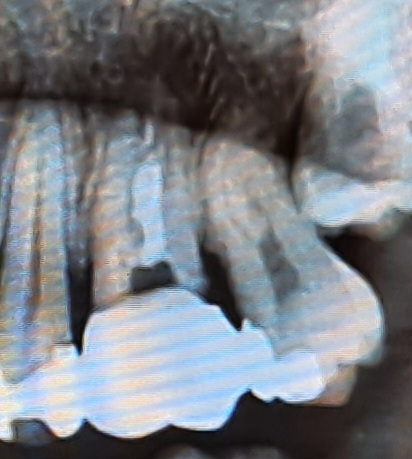

좌측 신경치료한 1대구친데 속이 뻥 비었고 치간칫솔시 냄새가 좀 납니다. 내부가 썩은 건가요? 2대구치 인레이한 부분도 썩은 건가요?

시경치료를 하고나서 크라운한 치아는 안쪽에 재료가 없어진거 같습니다. 아마 충치가 생겨서 그럴수도 잇으니 크라운 제거를 하고 상태를 확인해봐야 될것같습니다. 인레이 치료를한 치아 하방으로 충치가 생긴거 같긴합니다.

내부가 전체적으로 썩었고 상태도 안좋아보입니다. 재치료를 받으러 가시는 것이 좋겠습니다.

방사선사진상으로는 보철물의 경계부에 충치가 있는 것으로 보입니다. 인레이 주변에도 어두운 부위가 있지만 방사선상으로만 어두워 보이는 것일 수도 있기 때문에 좀더 자세한 검사가 필요해요.